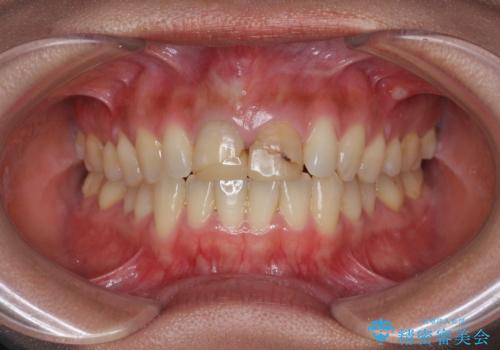

- 3週間後に迫った結婚式までになんとか前歯をきれいにしたいという希望で来院されました。

一回の治療時間を長く取り、限られた時間で最大限の結果を出せるよう集中治療を計画します。

ただ見えるクラウンを白くきれいにするのではなく、長期的な歯の予後を考えると根管治療・ファイバーコア築盛・精密な歯牙形成等クリアすべき条件は多々あると言えます。